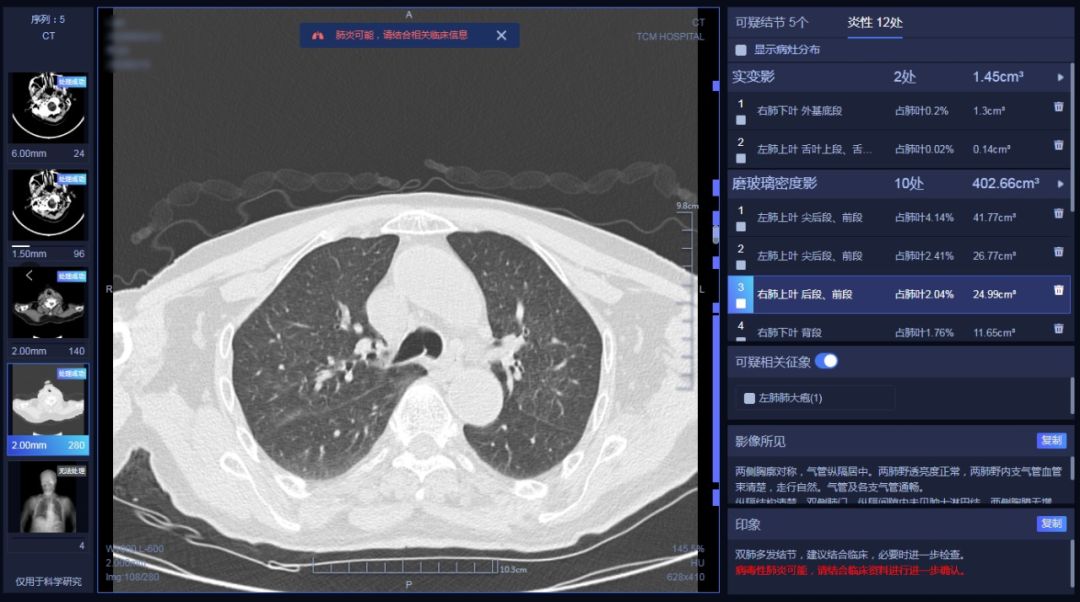

在响应国家号召和工信部倡议下,好心泰同时间赛跑、与病毒较量,积极投入技术研发中,针对新型冠状病毒,借助AI辅助诊断系统(新冠肺炎增强版),为抗击疫情提供诊前,诊中及诊后的全智能解决方案,好心泰采用的AI医学辅助诊断系统将在这里为一线疫情防控做出贡献。在Dr.Wise®全肺AI医学辅助诊断系统的基础上,结合本次新型冠状病毒感染肺炎的影像学表现,采用了Dr.Wise®肺部疾病智能解决方案(新冠肺炎增强版)针对不同类型肺炎的各种征象进行快速检测,同时强化新冠肺炎相似征象的检出,尤其针对局限性或多发,胸膜下及双肺野中外带,斑片影、磨玻璃影、网格影、条索影等征象具有很高的检出率。同时对于各种肺炎征象进行智能分类,对于实变和磨玻璃影进行定量分析,辅助医生判断肺炎分期及轻重程度,提供可疑肺炎疾病预警提示。最终为医生提供符合最新型冠状病毒指南的结构化图文报告。

新型冠状病毒发展迅速、在目前医疗资源紧张,医务工作人员工作量剧增的严峻形势下,借助人工智能技术可以高效的辅助当前新冠肺炎病例的大规模影像筛查,有助于及时发现潜在的患者,加强防控。Dr.Wise®肺部疾病智能解决方案(新冠肺炎增强版)提供全流程的诊疗管理,包括定位、定量分析、肺部CT炎症的多时点随访,标准结构化报告等,辅助医生大幅提升诊断效率,同时提高诊断准确性。无论是影像疑似病例确认为影像诊断病例,还是转归期患者确诊,多次CT复查随访都是必不可少的。“肺部疾病智能随访系统”可以针对同一患者的随访检查进行智能分析,对比病灶的变化情况,辅助医生对病情进展进行准确判断。